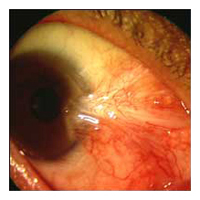

Before Pterygium Removal  After

Pterygium Removal

Dr. Jonathan Kao performs state-of-the-art pterygium removal surgery. He performs a complete excision of the lesion and will typically cover the area with what is called a conjunctival autograft.